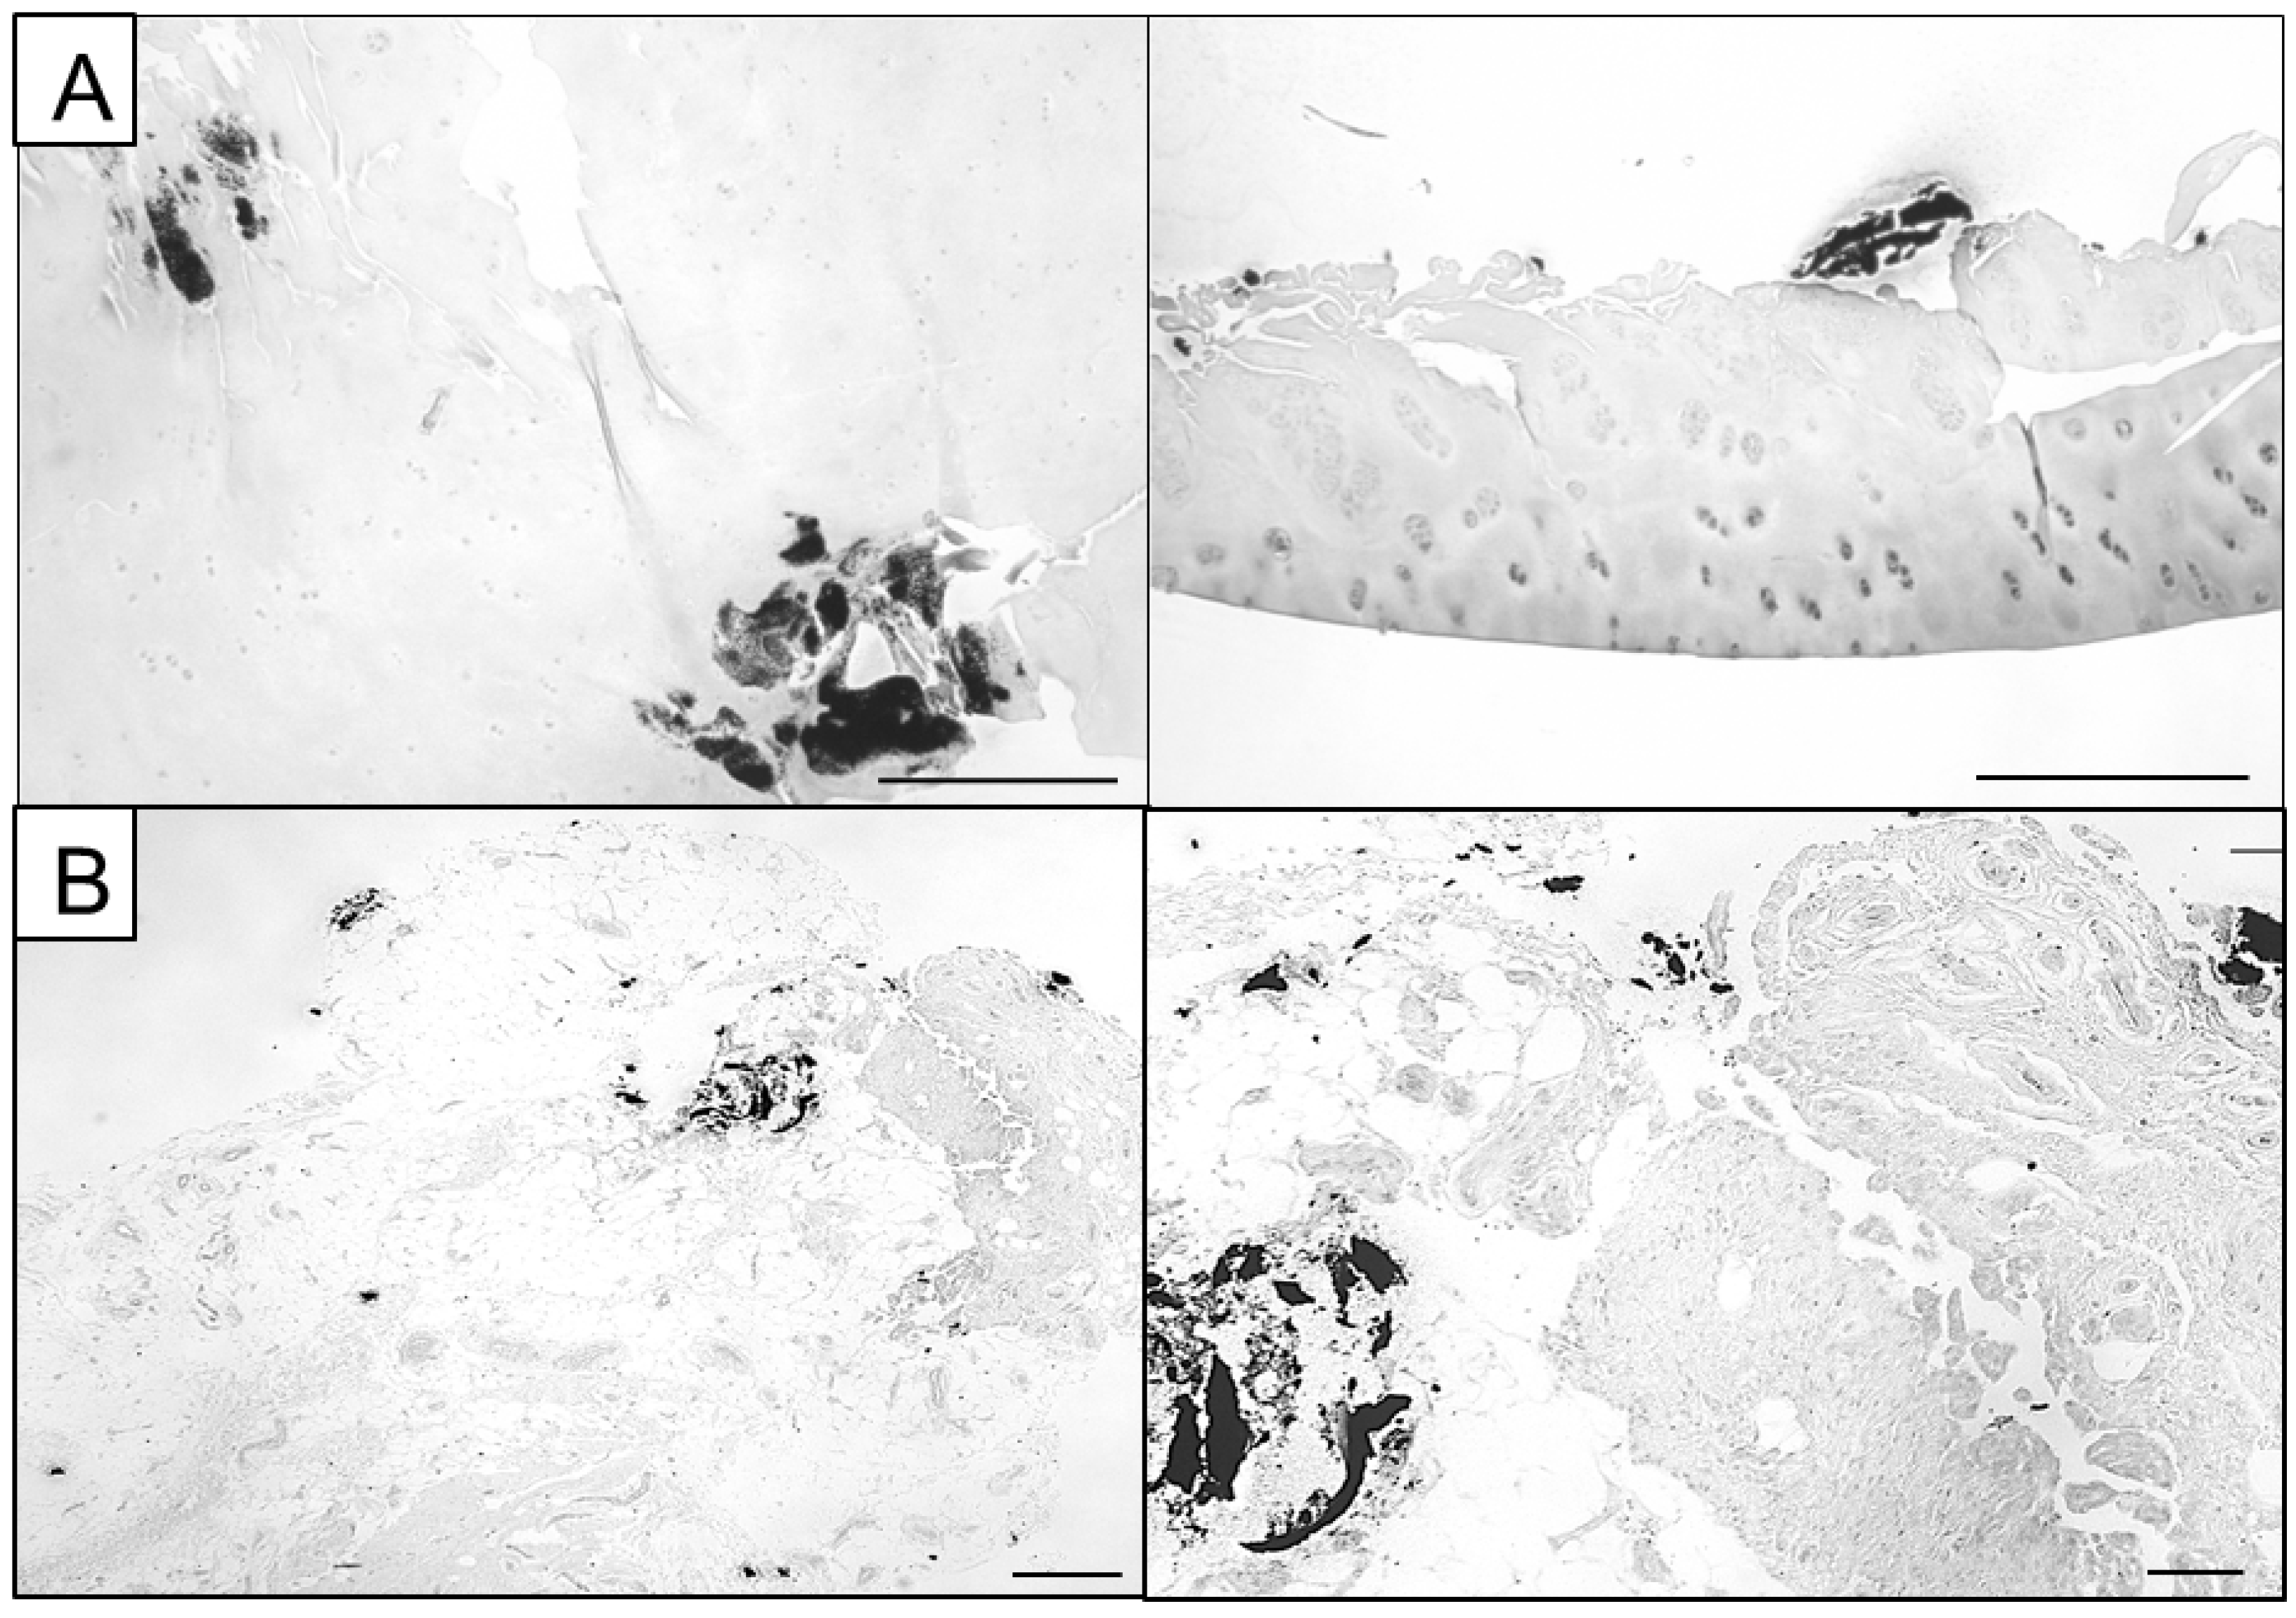

Alizarin Red S stains calcium in a red colour (Figure 1), while Von Kossa marks calcified areas in a black colour, easily visible against the light background (Figure 2). Alizarin red S binds calcium with a high affinity, forming a characteristic red chelation complex. However, the sensitivity of the stain strongly depends on the concentration and pH of the staining solution with overlapping optimal concentration and pH levels for BCP and CPP crystals, impeding accurate differentiation [38].

Figure 2.

Representative Von Kossa images of partly calcified joint tissue. (A) Calcifications can be embedded within cartilage tissue and located in the deeper layers exhibiting a powdery appearance (left panel) or presenting as calcified chunks located loosely at the chondrocyte surface (right panel, scale bars: 500 µm). (B) Synovial membrane specimens can exhibit both smaller calcifications and bigger calcified chunks that are integrated into the surrounding tissue or loosely presented aside (scale bars: 500 µm).

Von Kossa utilizes a two-step chemical reaction between silver ions and calcium phosphates, leaving a transient yellow colour. Under UV light exposure, organic matter reduces the bound silver ions to metallic silver, resulting in the characteristic black colour. Only the initial yellow colouration after the first reaction directly labels calcium phosphate while the later black colouration is a secondary result caused by organic material [39].

Further, multiple studies demonstrated discrepancies between Von Kossa-stained calcification nodules and spectroscopic detection of calcium phosphates, rendering Von Kossa staining alone insufficient for the identification and quantification of calcifications [25,40]. Therefore, high-resolution imaging techniques should be used to verify/identify the presence and nature of calcified deposits and improve their qualitative analysis. Here, we utilized Alizarin Red S (Figure 1) and Von Kossa images (Figure 2) to select ROIs for further microscopic and spectroscopic analysis.